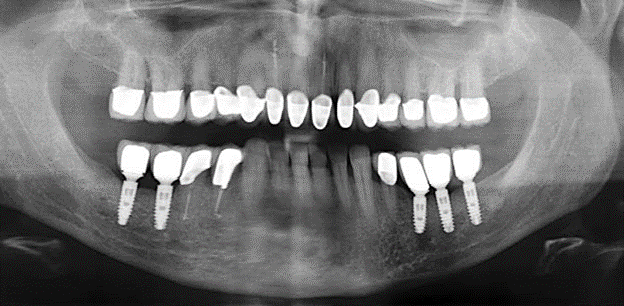

Un'assistenza standardizzata e regolare a misura di rischio nell'ambito di SPT è la chiave per il successo del trattamento clinico a lungo termine nei pazienti con situazione periodontale compromessa. Ciò è particolarmente vero per i pazienti a cui vengono applicati impianti dopo il trattamento parodontale completato con successo (Fig. 11a e b).